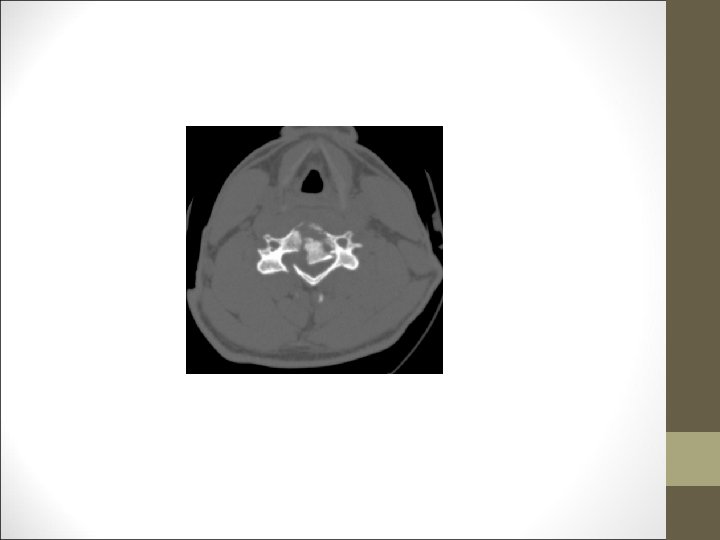

FACULTAD DE MEDICINA DEPARTAMENTO DE CIRUGÍA NEUROCIRUGÍA ¿Qué harías? TAC Cervical

TC Desplazamientos de fragmentos óseos ¿Algo mas? FACULTAD DE MEDICINA DEPARTAMENTO DE CIRUGÍA NEUROCIRUGÍA RM Desplazamientos discales y lesiones ligamentosa